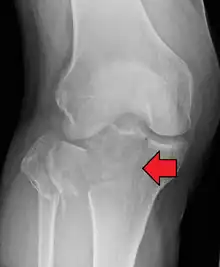

A tibial plateau fracture seen on X-ray

In all injuries to the tibial plateau radiographs (commonly called x-rays) are imperative. Computed tomography scans are not always necessary but are sometimes critical for evaluating degree of fracture and determining a treatment plan that would not be possible with plain radiographs.[5] Magnetic Resonance images are the diagnostic modality of choice when meniscal, ligamentous and soft tissue injuries are suspected.[6][7] CT angiography should be considered if there is alteration of the distal pulses or concern about arterial injury.